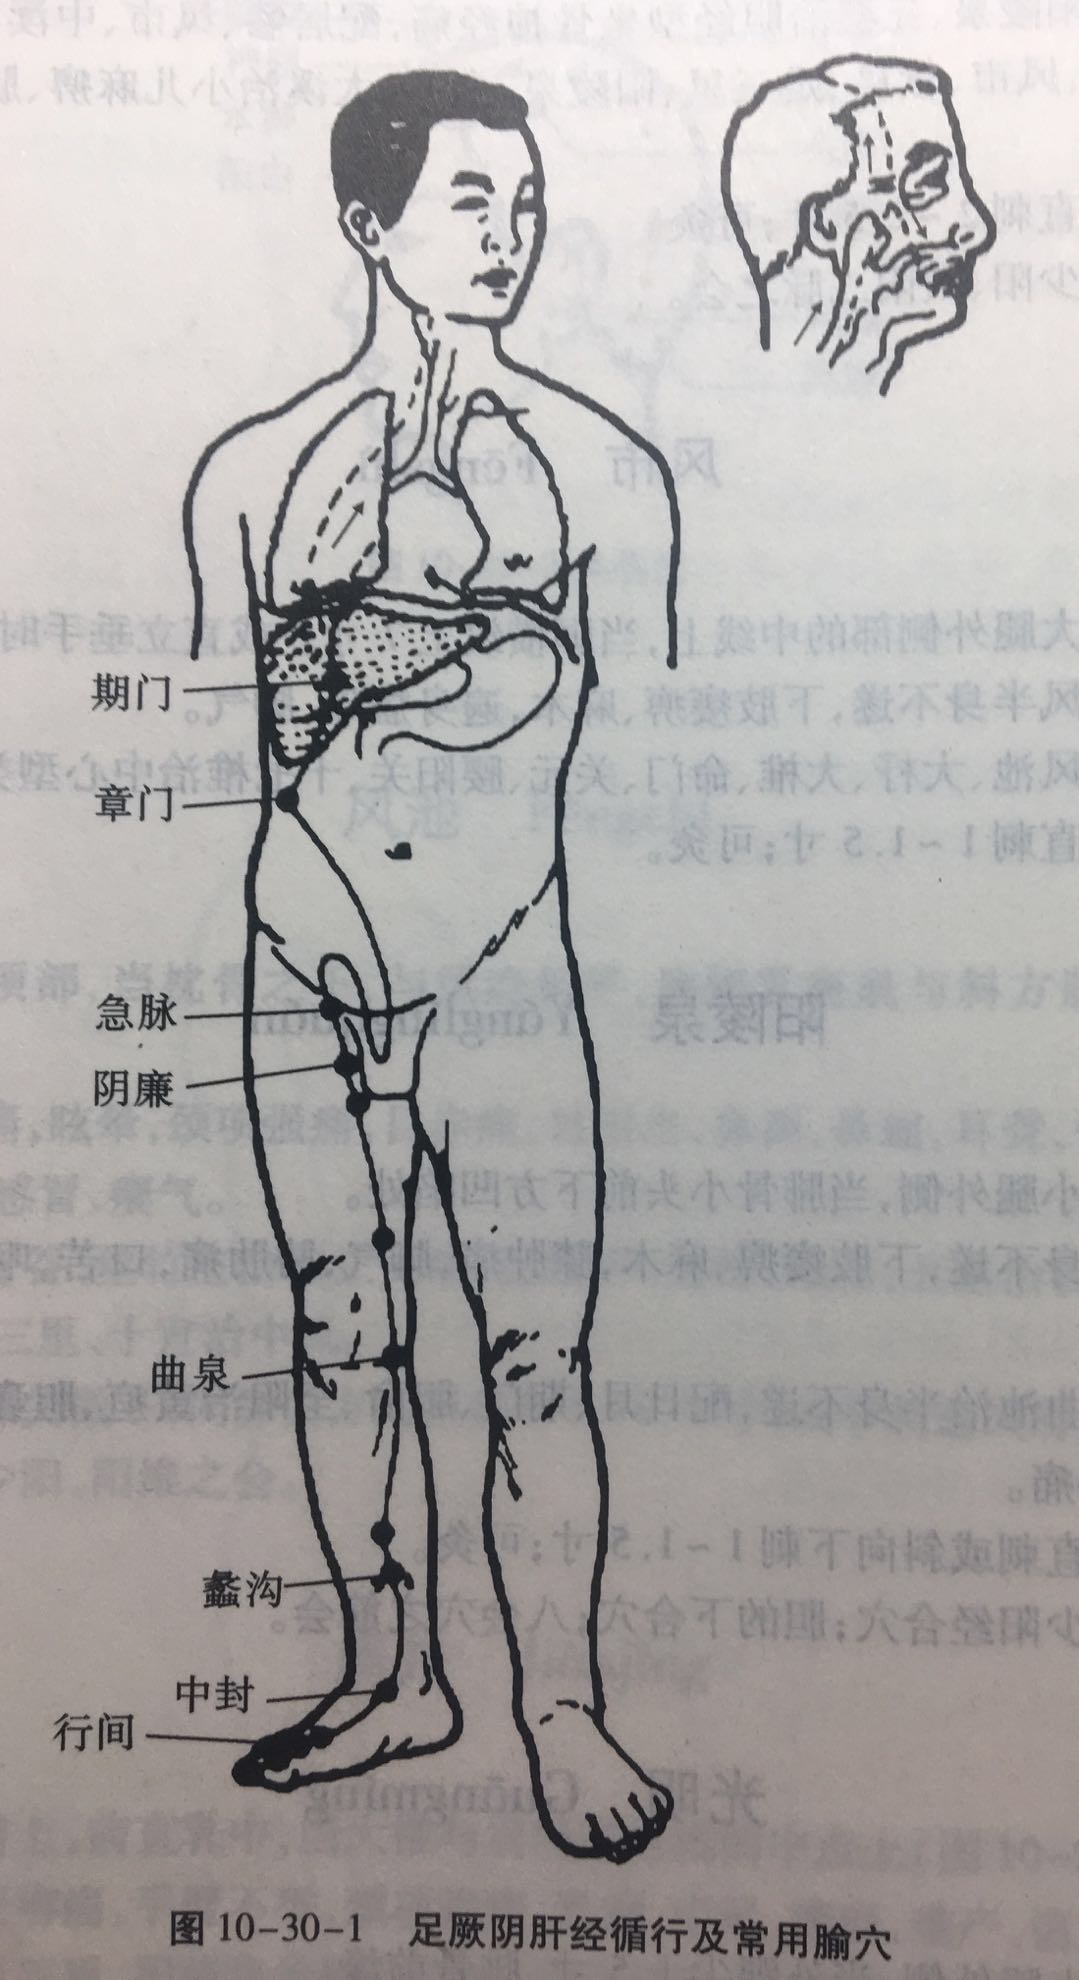

【(十二)足厥阴肝经(图10-30-1)】

1、时辰 丑时 1 ~ 3

2、歌诀 一十四穴足厥阴,大敦行间太冲侵,中封蠡沟中都近,膝关曲泉阴包临,五里阴廉急脉穴,章门常对期门深。

3、经脉循行 起于足大趾上毫毛部(大敦),经内踝前向上至内踝上 8 寸处交出于足太阴经之后,上行沿股内侧,进入阴毛中,绕阴器,上达小腹,夹胃旁,属肝络胆,过膈,分布于胁肋,沿喉咙后面,向上入鼻咽部,连接于“目系”(眼球联系于脑的部位),上出于前额,与督脉汇合于巅顶。

“目系”支脉:下行颊里、环绕唇内。

肝部支脉:从肝分出,过膈,向上流注于肺,与手太阴肺经相接。

4、主要病候 腰痛、胸满、呃逆、遗尿、小便不利、疝气、少腹肿等证。

5、主治概要 主治肝病、妇科、前阴病及经脉循行部位的其他病证。